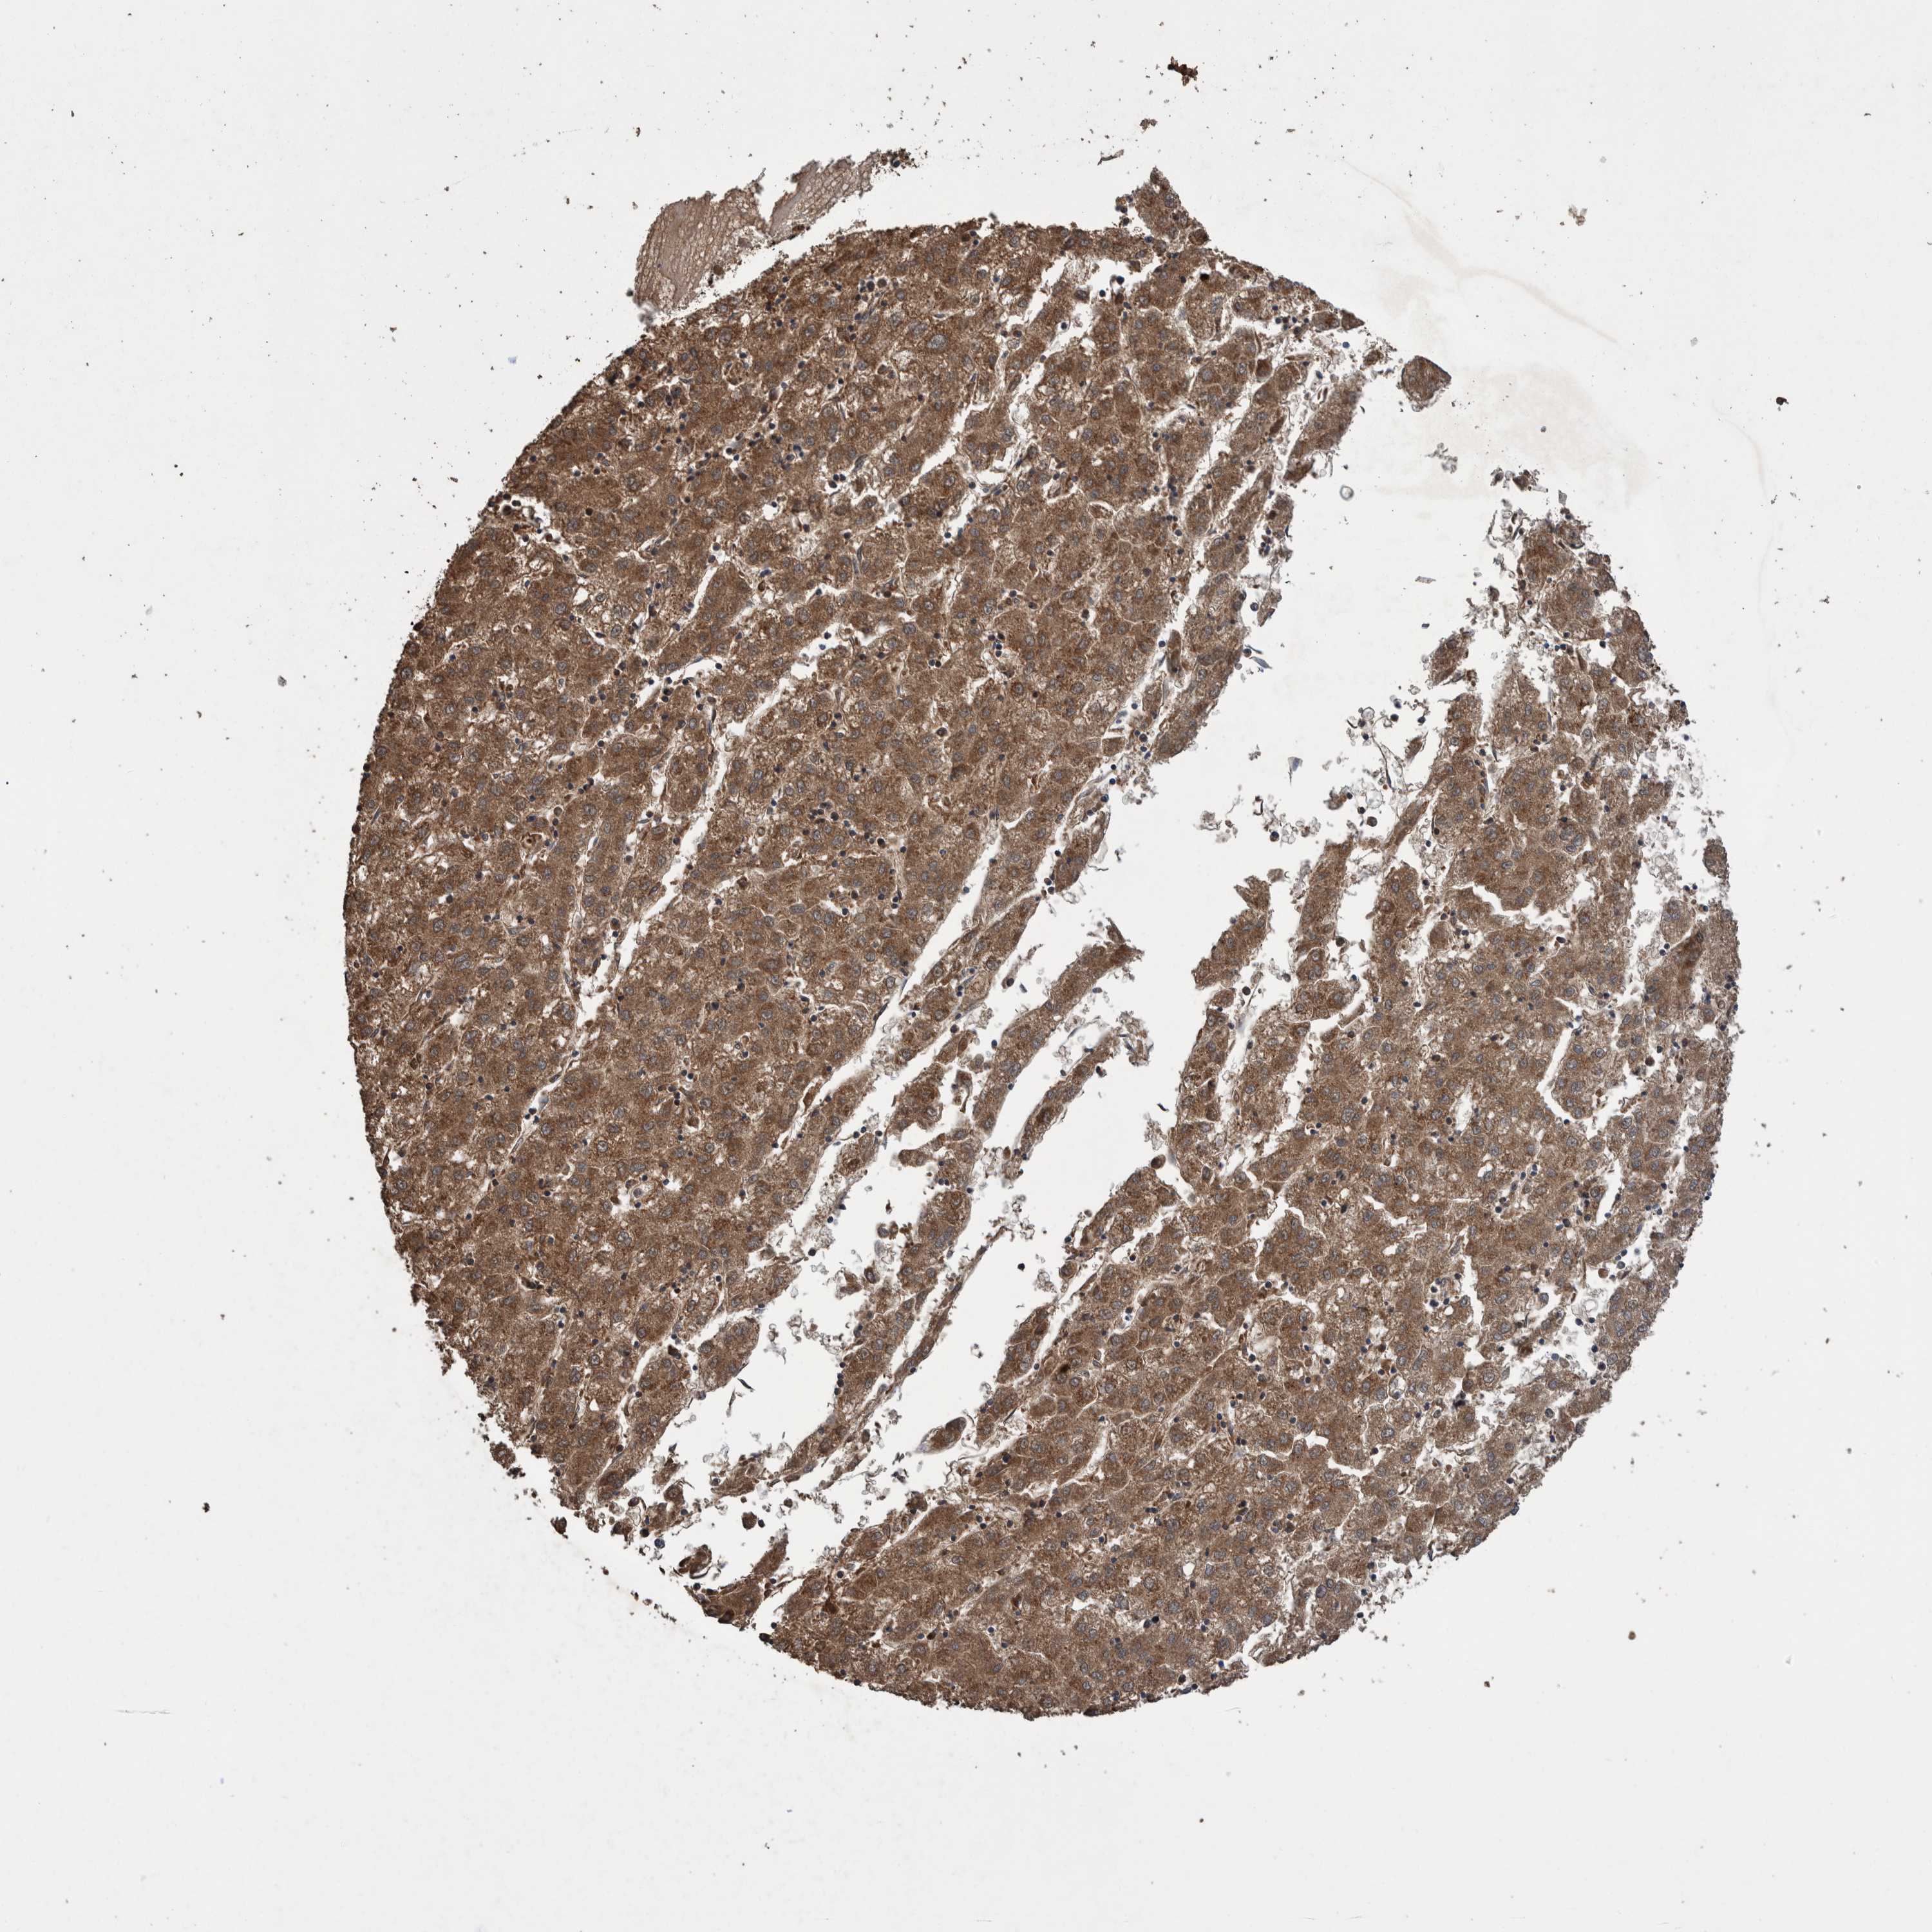

LIVER CANCER - Protein expressioni

A mouse-over function shows sample information and annotation data. Click on an image to view it in a full screen mode. Samples can be filtered based on level of antibody staining by selecting one or several of the following categories: high, medium, low and not detected. The assay and annotation is described here.

Note that samples used for immunohistochemistry by the Human Protein Atlas do not correspond to samples in the TCGA dataset.

Antibody stainingi

Antibody staining in the annotated cell types in the current human tissue is reported as not detected, low, medium, or high, based on conventional immunohistochemistry profiling in selected tissues. This score is based on the combination of the staining intensity and fraction of stained cells.

Each image is clickable and will lead to virtual microscopy that enables deeper exploration of all samples and also displays staining intensity scores, fraction scores and subcellular localization as well as patient and tissue information for each sample.

Antibody HPA023623

Antibody HPA066431

Staining

High

Medium

Low

Not detected

Intensity

Strong

Moderate

Weak

Negative

Quantity

>75%

75%-25%

<25%

None

Location

Nuclear

Cytoplasmic/membranous

Cytoplasmic/membranous,nuclear

Cholangiocarcinoma

Carcinoma, Hepatocellular, NOS